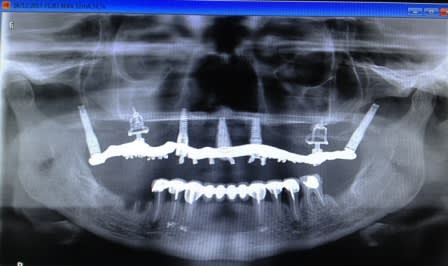

Ça ressemble bien à du Victory, avec des plaques en secteur 6.

On voit pas d'os autour des ptérygoidiens, c'est la radio ??

Moi non plus je vois que dalle autour des ptérygoidiens, je suppose qu'il doit bien y avoir un peu d'os autour!

les zygomatiques, c'est autre chose.

ici, bien des pterygo.

bf, bien mené, mais c'est peut être un poil sous équipé, non?

(plaques petit modele, 3 anterieurs)